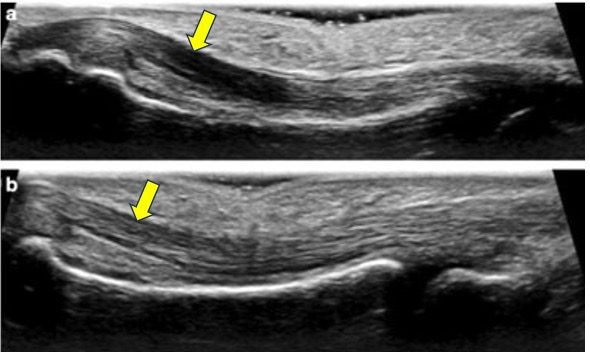

Figure 6. The top image (a) shows anisotropy artifact in the flexor tendon of the 3rd finger. The hypoechoic anisotropy artifact in the image was corrected in the lower image (b) by changing the angulation of the transducer to make the ultrasound beam hit the tendon at 90 degrees. This results in homogeneous echogenicity of the tendon. Image courtesy of ResearchGate.net. Be aware that if it was a true lesion such as tendinitis or tendon tear, heel-toe maneuver or other corrective techniques will not remove the hypoechoic region in the image.